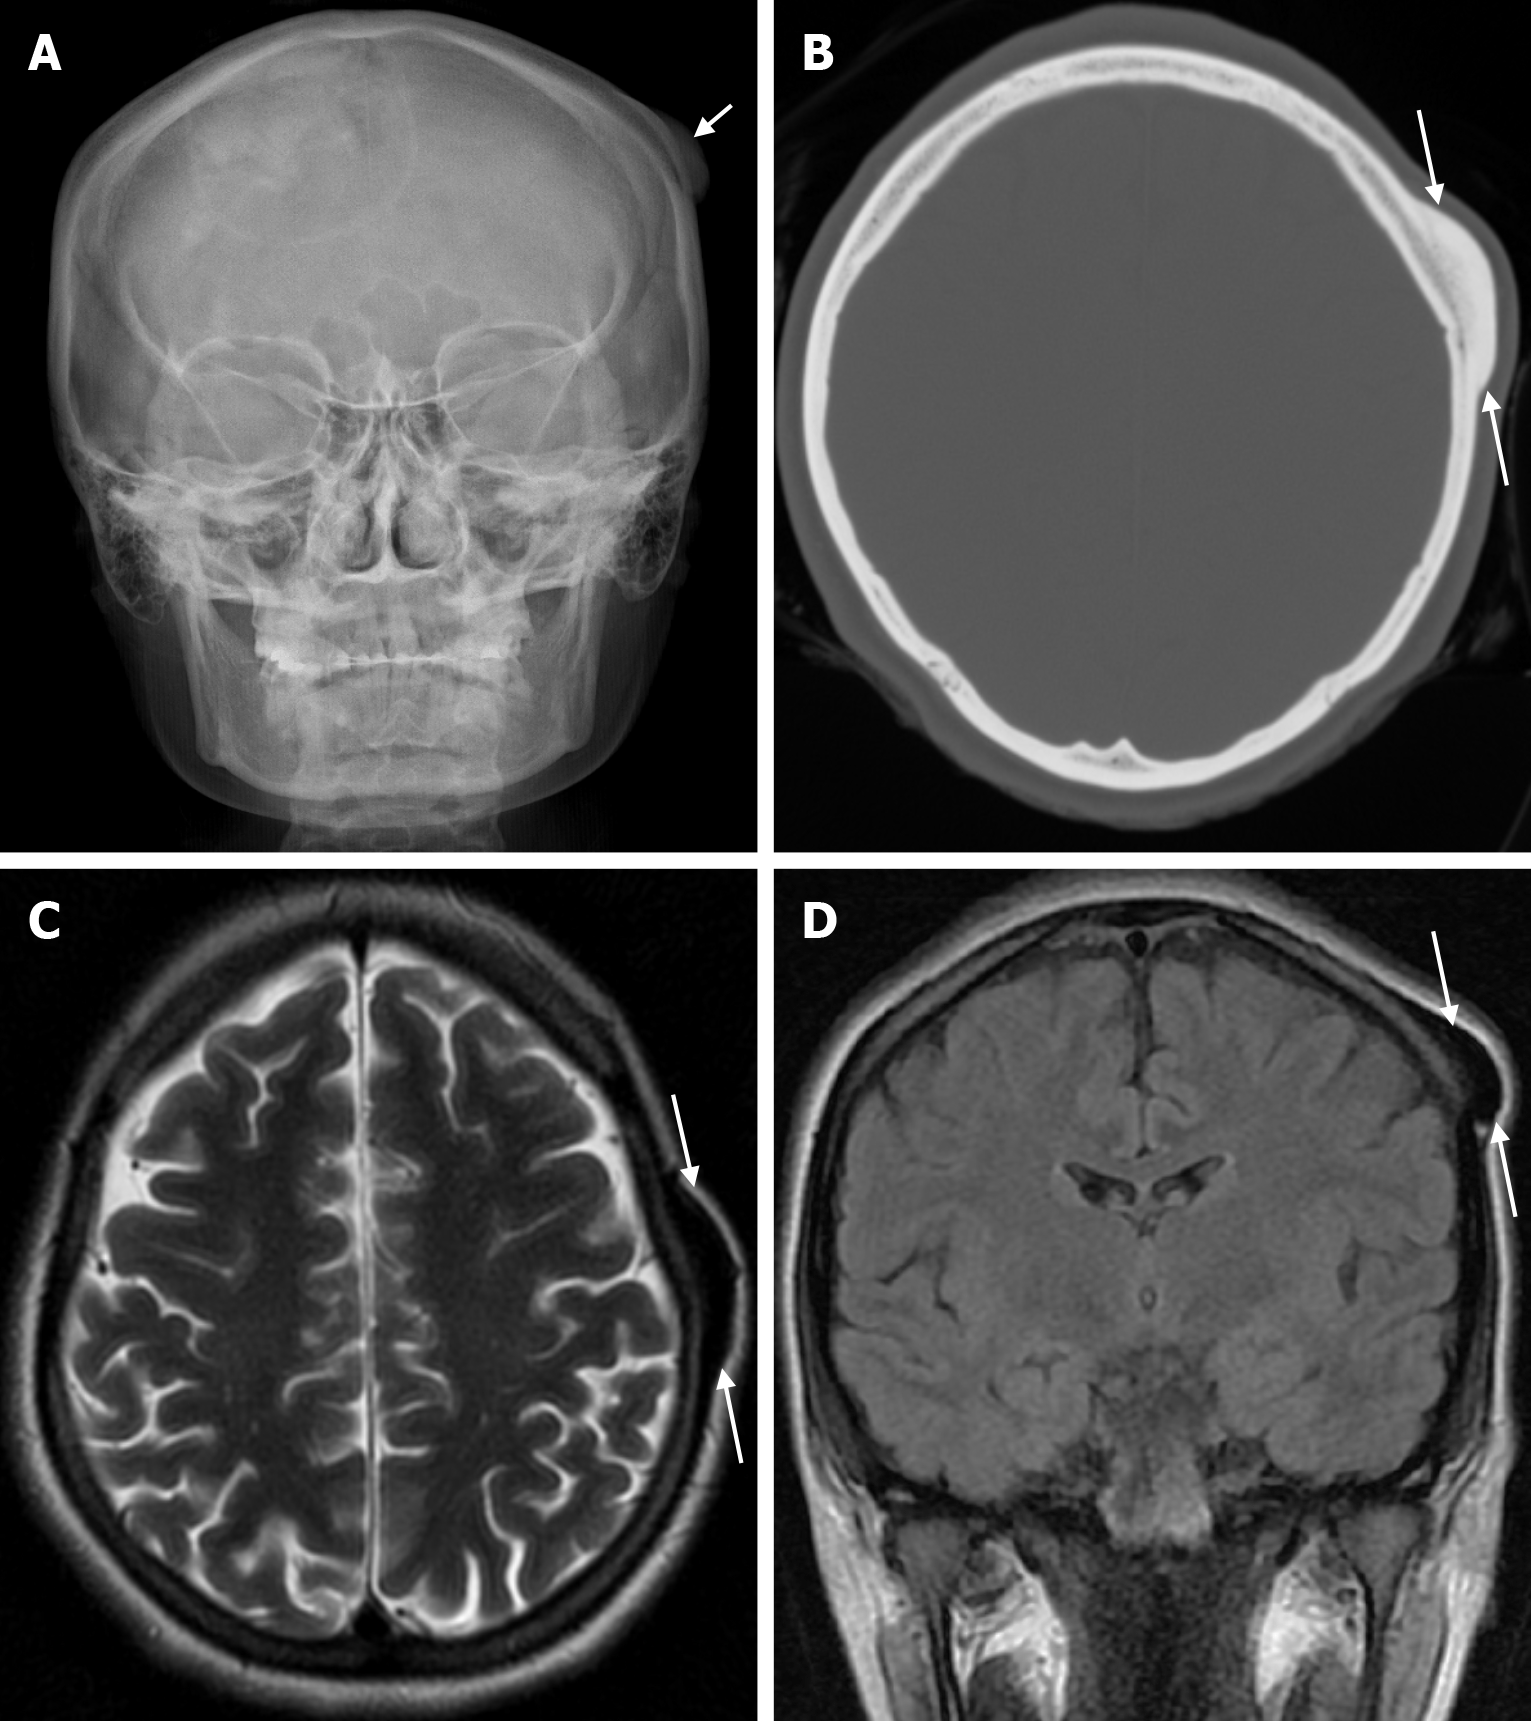

Arachnoid granulations (Pacchionian granulations) are cerebrospinal fluid-filled projections that extend from the subarachnoid space through openings in the dura into the venous sinuses and can be seen macroscopically. Their incidence varies from 0.3% to 55%. Arachnoid granulations are usually seen in millimeter dimensions, but may grow to fill the dural sinuses or arch the inner table[11]. In addition, intraosseous arachnoid granulations can sometimes extend to the inner table of the bone, causing scalloping, remodeling or bone erosion of the inner table[12]. The prevalence of arachnoid granulations increases with age, but there is no difference in gender distribution. Arachnoid granulations with a slight left hemispheric predominance are found in the dural venous sinuses, most frequently in the transverse sinuses and especially in the middle or lateral parts. The second most common location is the superior sagittal sinus, but they can be found anywhere in the dural venous sinuses. Arachnoid granulations are usually detected incidentally. If they fill and expand the dural sinuses, causing partial sinus obstruction, they may cause symptoms of increased intracranial pressure due to venous hypertension. They are usually associated with headaches. Arachnoid granulations may be seen as radiolucent areas on plain radiography of the skull or may cause compression on the inner table of the skull. On CT imaging, arachnoid granulations can be seen as sharply demarcated, hypodense structures in close relation to the dural venous sinus. On MRI, they usually show hyperintense signal on T2-weighted images and hypointense or isointense signal on T1-weighted images compared to brain parenchyma (Figure 1). On CT angiography, MR angiography or catheter angiography imaging, arachnoid granulations appear as oval or round filling defects in the dural venous sinuses during the venous phase[11]. Recent advances in radiology have made it possible to identify brain herniations into the arachnoid granulation by improving image quality with higher resolution and thinner slice three-dimensional T1-weighted and T2-weighted MRI sequences (Figure 2). Brain herniation into the arachnoid granulation is rare in the literature, and the incidence of brain herniation into the calvarial or dural sinuses has been reported to be 0.32%[13]. Arachnoid granulations may be confused with pathological processes in the dural venous sinuses[11]. In the differential diagnosis of arachnoid granulations, venous sinus thrombosis, dural-based tumors, or structures such as septa and fat that may cause filling defects in the dural venous sinuses should be considered[12]. Dural sinus thrombosis usually fills an entire sinus segment or several sinuses and may extend to the cortical veins, whereas arachnoid granulations appear as focal and well-defined defects. Fresh thrombus in the dural sinuses are hyperdense on CT and hyperintense on T1-weighted MRI. Differential tumor diagnosis can be made based on its shape, lack of contrast enhancement and diffusion restriction[11].

Epidermoid cysts are small or medium-sized, benign, and slow-growing tumors that arise from the remnants of ectodermal cells in the bones of the skull. These cysts can also develop after trauma or surgery. Epidermoid cysts are lined with squamous epithelium. They contain deposits of cholesterol and keratin. These cysts constitute less than 1% of primary intracranial tumours, while intradiploic epidermoid cysts account for less than 0.25% of intracranial tumours. These tumors can occur at any age from the first decade of life to the seventh decade, with a mean age of 32-38 years, and there is no gender predilection. Epidermoid cysts are most commonly found in the frontal, parietal and occipital regions and often involve more than one bone. Epidermoid cysts appear on plain radiography as round or lobulated lytic areas with smooth and sclerotic margins. On CT they appear as non-contrast enhanced intradiploic lytic hypodense lesions with smooth sclerotic borders. Epidermoid cysts often cause remodeling and widening of the inner and outer tables. Epidermoid cysts that appear hyperdense on CT due to bleeding, calcification or high protein content are called white epidermoids and are observed quite rarely. On MRI, epidermoid cysts appear isointense/hyperintense on T2-weighted and fluid-attenuated inversion recovery (FLAIR) images and slightly hyperintense on T1-weighted images (Figure 4). These lesions restrict diffusion on diffusion-weighted imaging but show no contrast enhancement on contrast enhanced sequences[19].